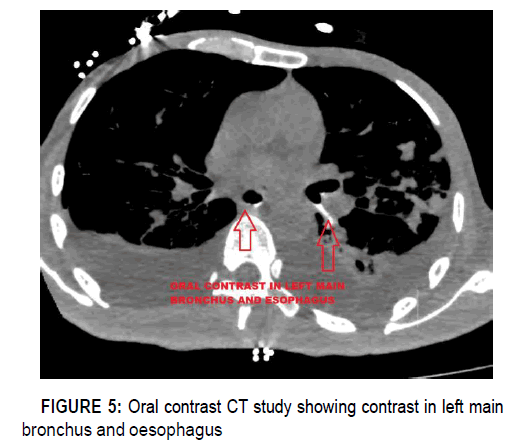

Bronchial wash was done, and samples sent for bacteriology tests, XPERT MTB and cytology and were non-contributory. Because of a suspected tracheo-oesophageal fistula, the patient underwent oral contrast computed tomography (CT) study. It showed evidence of oral contrast in the left main bronchus, suggestive of Left main broncho-oesophageal fistula.

clinical-case-reports-bronchus-oesophagus

Figure 5: Oral contrast CT study showing contrast in left main bronchus and oesophagus